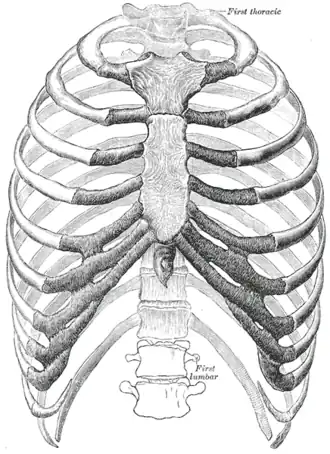

The thorax from in front. (Superior thoracic aperture visible at top.) | |

Structure

The superior thoracic aperture is essentially a hole surrounded by a bony ring, through which several vital structures pass. It is bounded by: the first thoracic vertebra (T1) posteriorly; the first pair of ribs laterally, forming lateral C-shaped curves posterior to anterior; and the costal cartilage of the first rib and the superior border of the manubrium anteriorly.

The adult thoracic outlet is around 6.5 cm antero-posteriorly and 11 cm transversely. Because of the obliquity of the first pair of ribs, the aperture slopes antero-inferiorly.